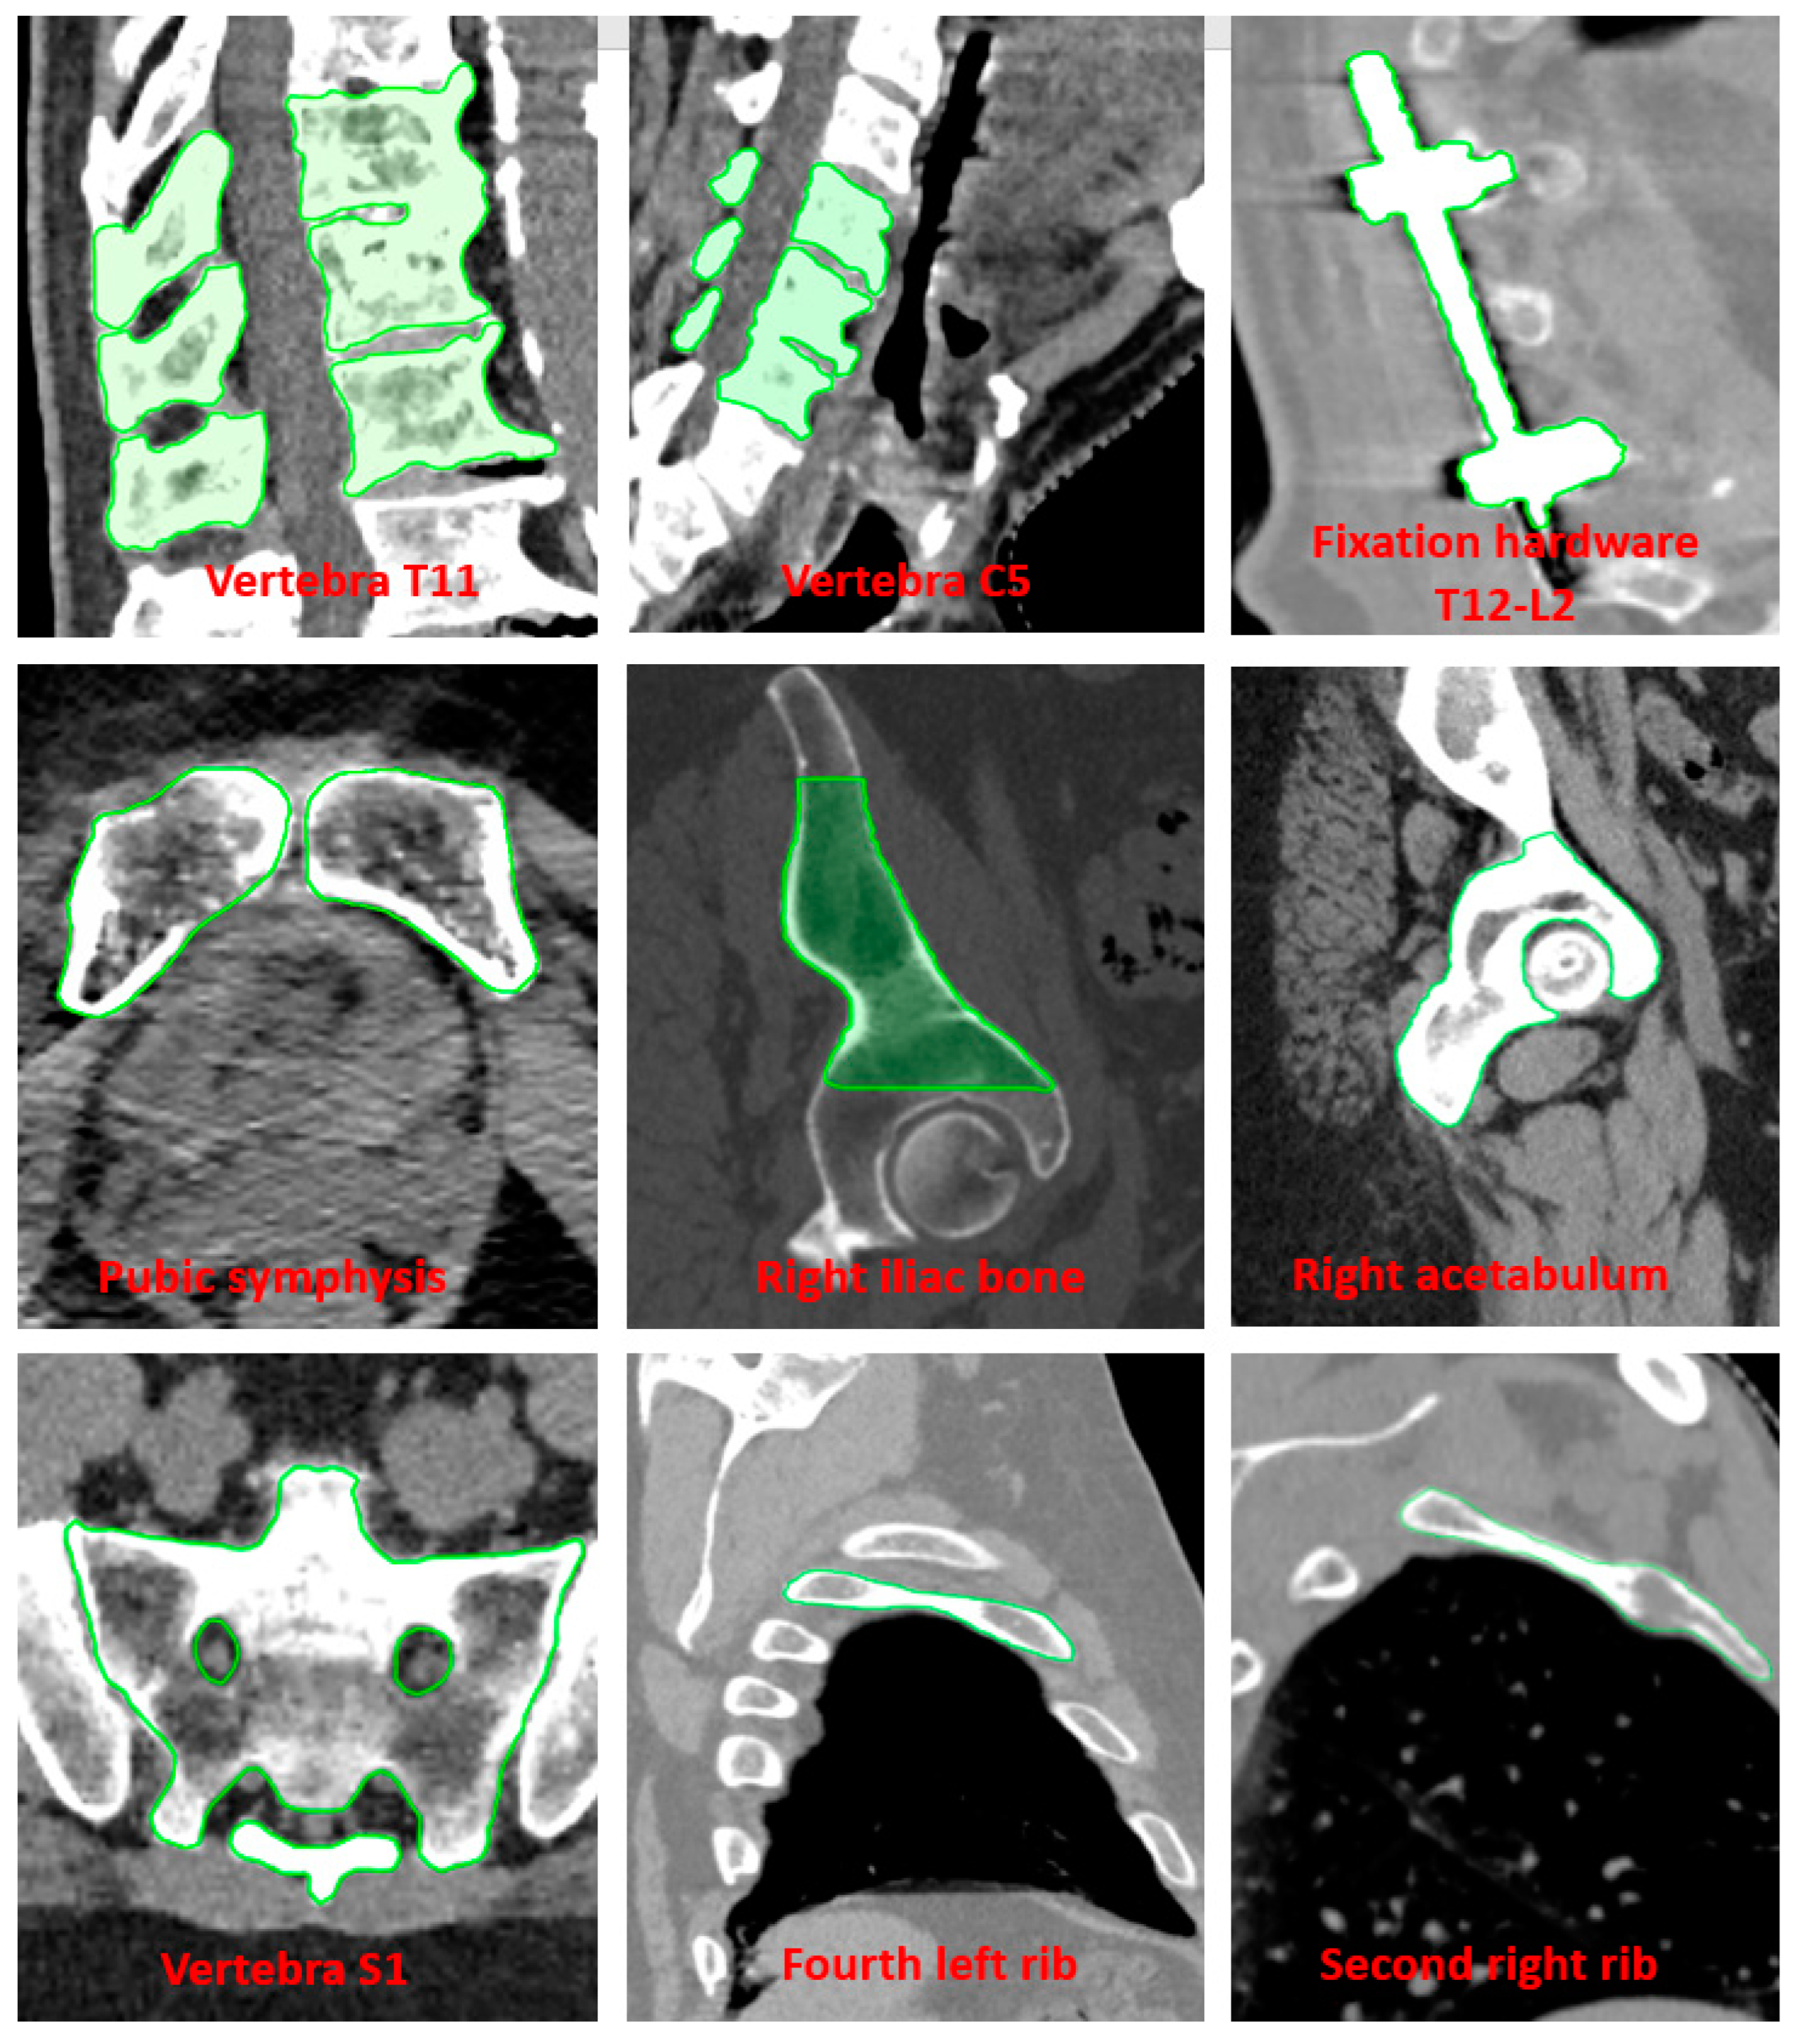

2. Materials and Methods

2.2. Patient Study